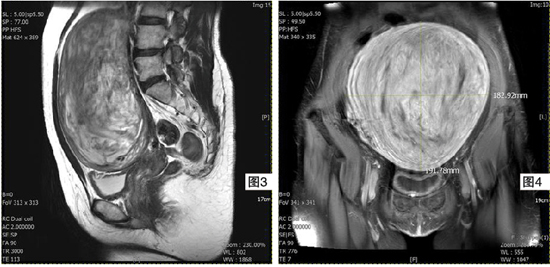

作为放射治疗科医生,我们主要使用有着高分辨率的磁力共振造影(MRI),在子宫肌瘤检测中,可达86%至92%敏感度、100%的特异性与97%准确度(accuracy)。通过MRI扫描,医生除了可以准确地鉴别子宫肌瘤或子宫肌腺瘤,也能够确认病灶数量、位置与检查子宫周边的结构,通常呈白色的肌瘤是单纯由平滑肌细胞组成;而呈黑色的通常是混合了子宫肌腺瘤。

值得注意的是,子宫肌瘤与子宫肌腺瘤可同时存在。我在临床上曾遇见一名患者,她是44岁的单身小学教师,通过MRI扫描发现,子宫里的肿块中有30%为纯肌瘤、30%为子宫肌腺瘤,另40%则是两者混合在一起,在治疗上较为棘手。

要知道由于子宫肌腺瘤所形成的异常组织,与正常组织没有明确的界线,所以不容易透过手术去切除干净。若女性患有单纯的子宫肌瘤,则有许多方法解决,譬如荷尔蒙药物、子宫切除术、子宫肌瘤切除术(myomectomy) 、子宫动脉栓塞术(UAE)、高强度聚焦超声波(HIFU,又称海扶刀)、射频消融(RFA)、微波消融(MWA)等,但若子宫肌腺瘤占更多,那么荷尔蒙治疗效果会减少。对此,她的唯一选择为UAE,因为无论是HIFU或 RFA等,只适合针对局部一二处病灶,无法治疗混合子宫肌瘤、大范围和弥漫型的子宫肌腺瘤。